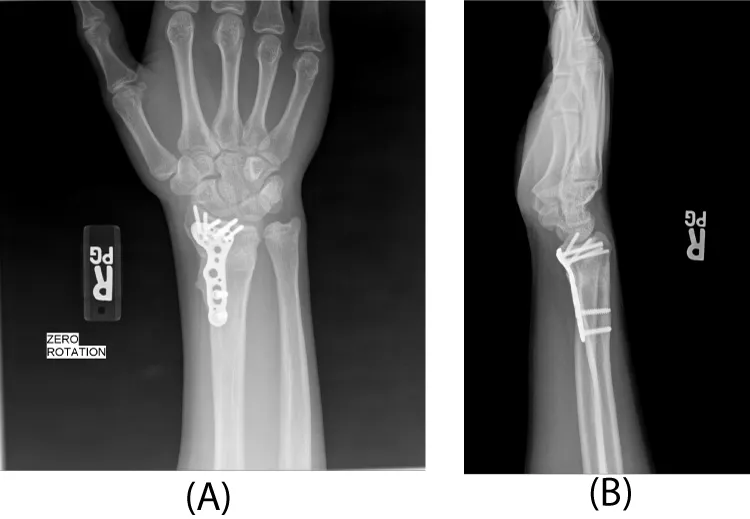

After pre-operative education and informed consent was obtained, the patient was taken back to the operating room for a complex distal radius osteotomy. Care was taken to recover radial length and realign the sigmoid notch of the distal radius relative to the head of the ulna at the distal radioulnar joint per the pre-operative plan and template. In order to recover length, the plate was first applied to the radius and then removed for the osteotomy. It was then reapplied to the distal fragment with locking screws. The plate was then reduced to the radial shaft proximally. Once length was obtained, the radius was secured to the radial shaft with a locking and a non-locking screw (Figure 5). The large trapezoidal metaphyseal defect was then filled with pure cancellous autograft obtained from the ipsilateral iliac crest (Figure 6). A 40mm acetabular reamer was used for this purpose, starting on the outer table and reaming toward, but not violating, the inner table. The remaining radial physis that remained open (ulnarly) was closed with a small burr under image control. The distal ulnar physis was similarly closed through a small ulnar incision to prevent further progression of growth mismatch (Figure 7). At 3 months following the osteotomy, radiographs showed complete healing with incorporation of the bone graft. In addition, the distal ulnar physis had closed. The patient regained full wrist range of motion with 75o extension, 90o flexion, 85o pronation and supination. This was symmetric with his contralateral side. His grip strength was 80 pounds bilaterally. He denied any pain or wrist symptoms and returned to sports and weightlifting. Final follow-up at one year revealed full mobility and symmetrical wrist and forearm motion (no measureable side to side differences). Radiographs showed maturation of the bone graft with remodeling (Figure 8).

Once physeal arrest occurs in the radius and affects wrist and forearm anatomy, including the distal radioulnar joint, various treatment options exist [9-12]. Patients can undergo a lengthening osteotomy of the radius, a shortening osteotomy of the ulna (typically with closure of the ulnar physis), or a combination of the two [1,10,11]. Due to the gross three dimensional deformity present in our patient with reversal of the normal radial inclination, we chose to realign the wrist and forearm by correcting the radius alone. While an additional shortening of the ulna could have been considered, we found this not to be necessary intra-operatively. In addition, we did close the remaining physis of the radius and that of the ulna.

With the significant lengthening of the radius, a very large trapezoidal defect remained. We chose to fill this with non-structural bone graft, rather than a more traditional corticocancellous bone block. This was facilitated by the use of a locking plate, which maintained the three-dimensional anatomy of the reduction during healing.